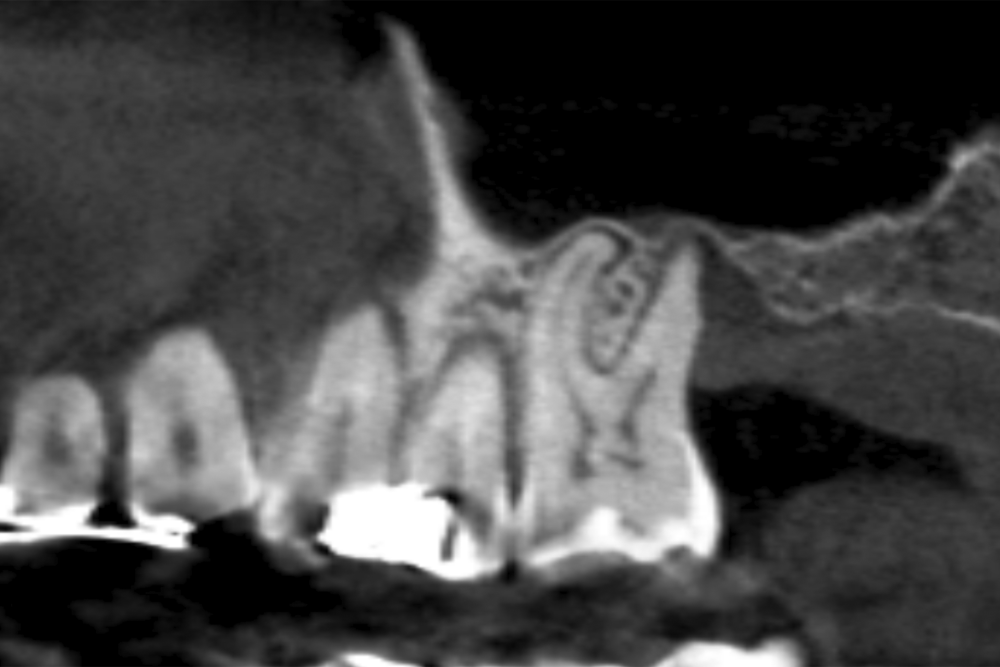

Figures 2-19 show one of the cases included in the study.

In all cases, a diagnosis was made based on study models, intraoral examination of the patient and performing a Cone-beam analysed using the specific BTI-Scan 3 software (Biotechnology Institute, Vitoria, Alava, Spain).

Patients attend subsequent check-ups performing a control Cone-Beam after 5 months (before loading the implant) and after one year of the load, performing a new measurement in these images to analyse the bone gain and the maintenance of the same. In these check-ups, data are collected on prosthetic complications or crestal bone loss in these patients, as well as possible failures.

The mean height of the residual bone volume was 3.1 mm (+/- 0.3 mm with a range of 3-4 mm). In all cases, transcrestal sinus elevation was performed, with particulate autologous bone obtained from milling the neo alveolus generation zone for implant insertion, being the average of this elevation above the apex of the implant of 2.8 mm (+/- 0.99 range 1.9 -5 mm). In the CT control scan after one year of inserting the studied implants, the bone gain achieved was maintained, no decrease in the volume gained was observed, only three cases showed a decrease of between 0.4 and 0.5 mm of the initial volume at the end (Table).